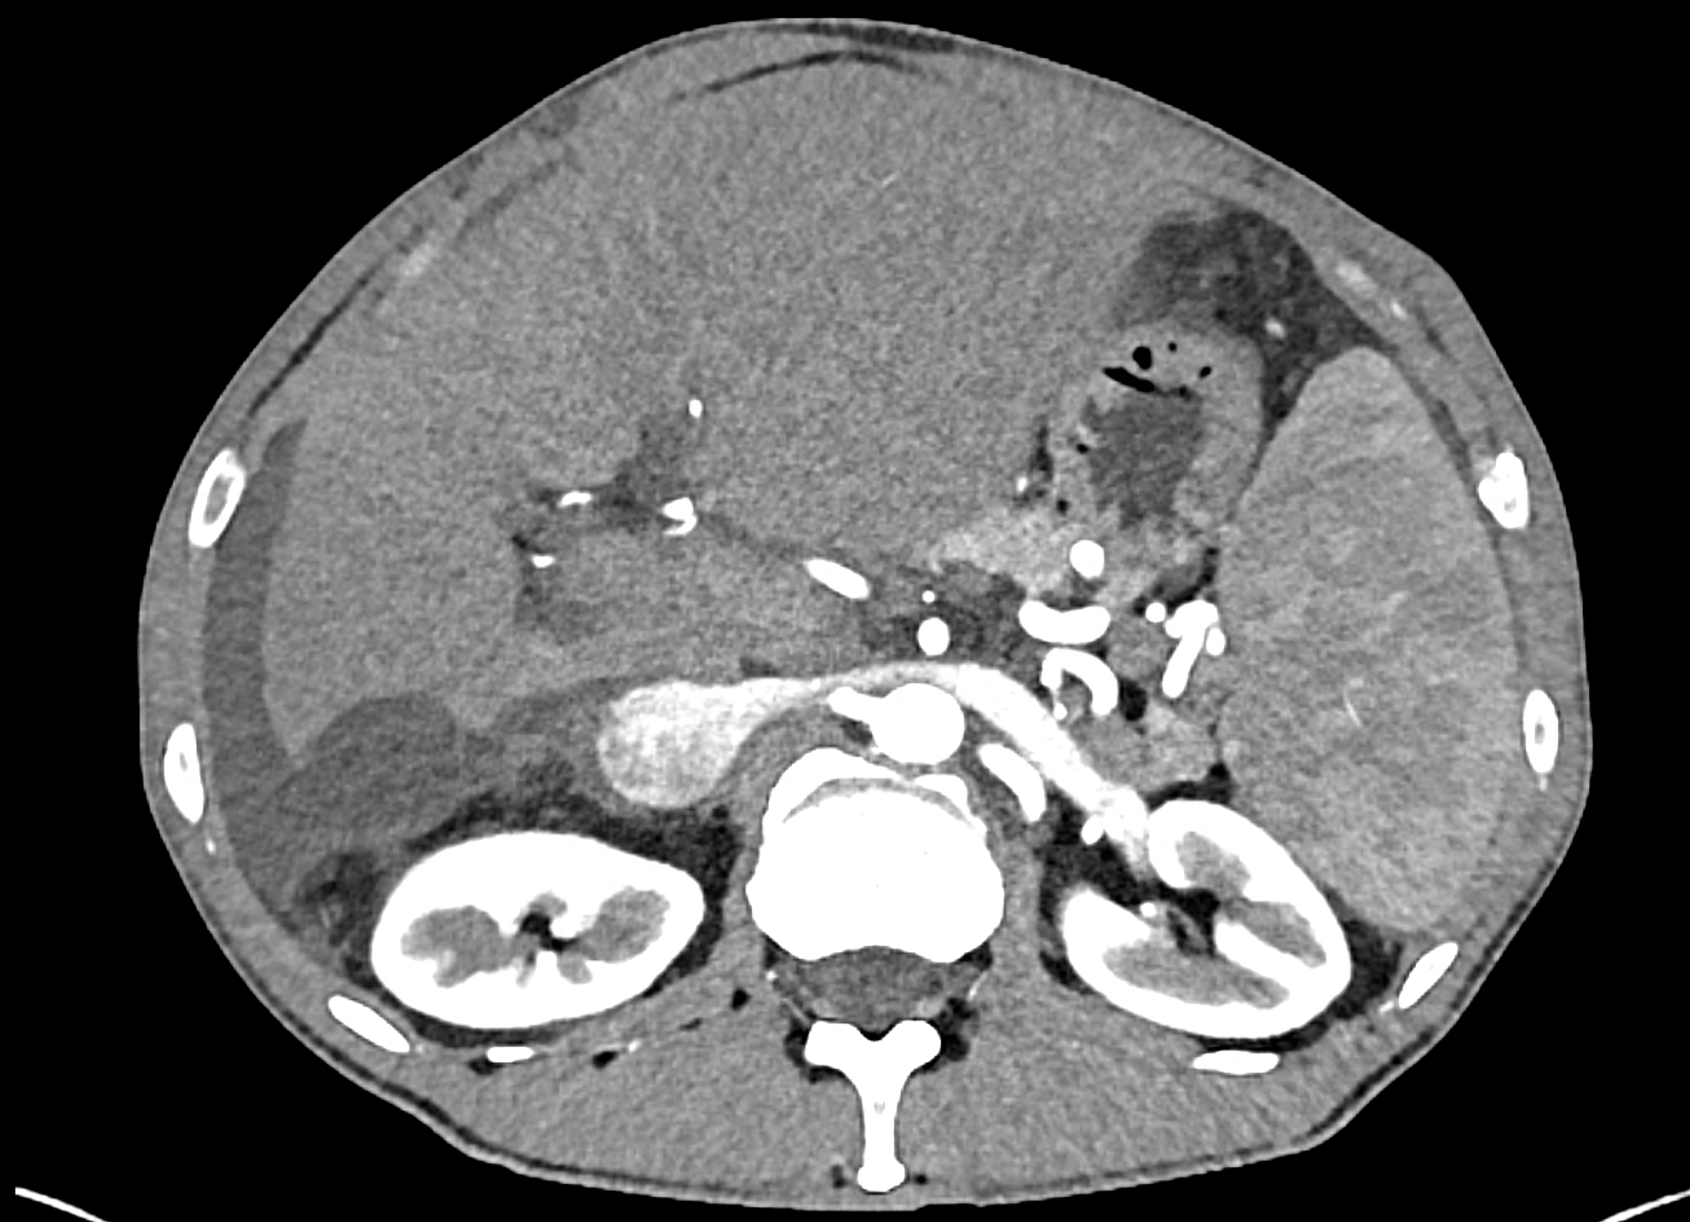

In CT images, BCS manifests as non-homogeneous enhancement of liver tissue in the arterial and especially in the portal phase, although in the portal phase may be increased, especially in the caudate lobe and left lobe, which are often hypertrophic (the hypertrophy and the enhancement is caused due to the possibility of the venous drainage directly into the inferior vena cava through the direct caudate veins), in contrast to the reduction in the right lobe. The portal vein is free, whereas even in the late phase, the hepatic veins and their contrast filling are not visible. Thrombotic occluded veins are hypodense.

A patient in his sixties with a Leiden mutation of factor V and a heterozygous prothrombin mutation presents with abdominal pain. Ultrasound examination reveals ascites and enlargement of the liver.There is enlargement of the liver, particularly the left lobe and caudate lobe. The hepatic veins are centrally filled with contrast medium due to reflux at the confluence with the inferior vena cava, and their radicular parts are thrombosed. There is typical chronic liver remodelling and the formation of centrifugal collateral circulation, including esophageal varices, and ascites is present in the abdominal cavity.

the axial images in the arterial, and the portal phases